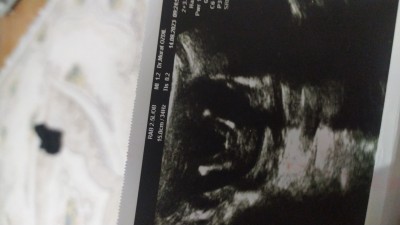

Cinsiyet 15+4 tahmin

Kizlar 15+4 sizce cinsiyet ne doktor erkek dedi

Doktor erkek dediyse, erkek demek ki. Sağlıkla büyüsün inşallah.

Bana kız gibi geldi (!)

Bence kiz bacak arası boş